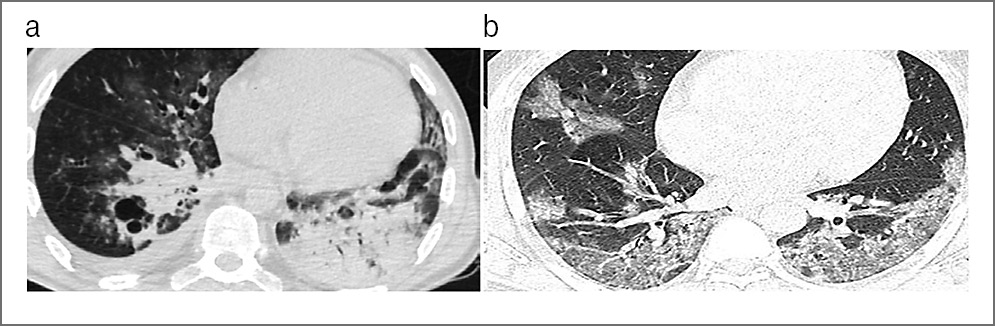

В качестве примеров приводим КТ органов грудной клетки, иллюстрирующую сходство КТ-признаков у больных 1 и 2-й групп, с этиологической верификацией бактериальной пневмонии (вызванной S. aureus) с COVID-19 (рис. 1, а) и без COVID-19 (рис. 1, b); микобактериозом легких (обусловленным M. avium complex) с COVID-19 (рис. 2, а) и без COVID-19 (рис. 2, b); пневмоцистной пневмонией (вызванной P. jiroveci) с COVID-19, ТОД (рис. 3, а) и без COVID-19 (рис. 3, b) и вирусной пневмонией (вследствие инфекции Cytomegalovirus hominis) с COVID-19, ТОД (рис. 4, а) и без COVID-19 (рис. 4, b).

Рис. 4. КТ органов грудной клетки. Аксиальная проекция, режим легочного окна: а – пациент, 26 лет, с 4B-стадией ВИЧ- инфекции в фазе прогрессирования, без АРВТ и верифицированной коинфекции COVID-19, ТОД и вирусной пневмонией (вызванной Cytomegalovirus hominis); b – пациент, 29 лет, с 4B-стадией ВИЧ-инфекции в фазе прогрессирования, без АРВТ и верифицированной коинфекции ТОД и вирусной пневмонией (вызванной Cytomegalovirus hominis).